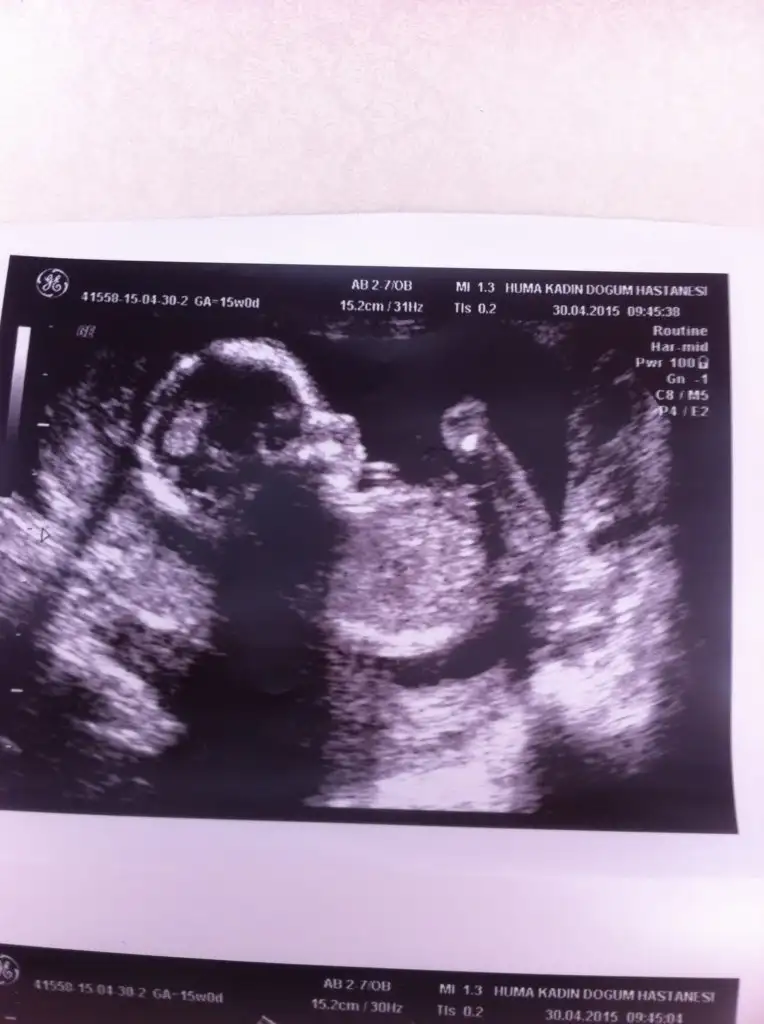

Kızlar merhaba Benimkiler ikiz 13 haftalıklar. Dun doktoru baya zorladım. Oda ikisinde kız dedi :) pipi göremedim dedi. Ama okadar kalitesiz ultrason aletiydiki anlatamam. Su resimden anlayabilir misiniz.

Eklentiler

• IMG_20150429_140851.webp

IMG_20150429_140851.webp

18,7 KB · Görüntüleme: 154

Tek yumurta ikizi sanırım :) ama bencede kız gibi bu açıdan.

Bende senin gibi düşünüyorum. O görünen ayak Oluşumu gibi bacaklarının arasında nubu paralel duruyo. Kız bebek gibi.

Alttaki kız gibi duruyo çünkü dikkatli bakınca paralel gibi. Üsttekine emin değilim o da kız gibi duruyo ama tam değil bence. Doktorun tecrübesiyle ultrason makinesi kötü olsa bile anlıyorlar :)